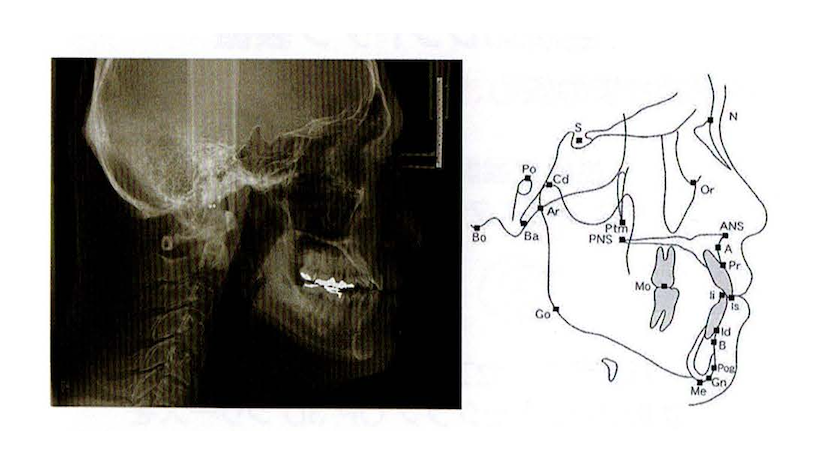

セファロ撮影(矯正治療用のレントゲン)

🩺 特徴

・頭部全体の骨格や歯の位置を横から撮影

・歯並びやかみ合わせ、顎の成長を分析できる

・矯正治療の診断や経過観察に欠かせない

😊 患者さんにとってのメリット

✔ 矯正治療をより精密に計画できる

✔ お子さんの成長に合わせた矯正治療の判断が可能

✔ 顎の位置やバランスを正確に把握し、治療後のシミュレーションができる

💡 こんなときに役立ちます!

・歯列矯正を考えている方

・お子さんの顎の成長を確認したい方

・かみ合わせのバランスを診断したい方